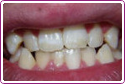

Patrycja ma 15 lat. Górne jedynki były przebarwione od antybiotyków.

Rozwiązanie – profesjonalne wybielanie zębów.